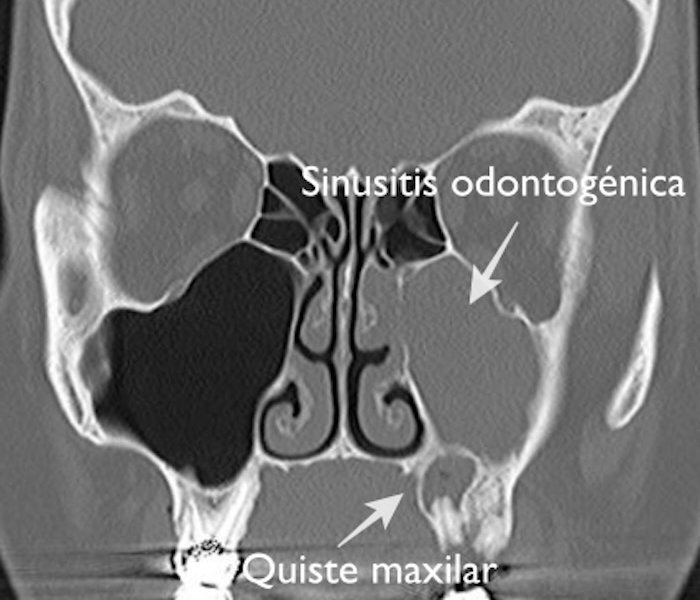

La sinusitis odontogénica es la infección de la mucosa de los senos maxilares causada por una caries complicada en las muelas superiores que transmiten la infección al seno a través del conducto de la raíz.

sinusitis maxilar